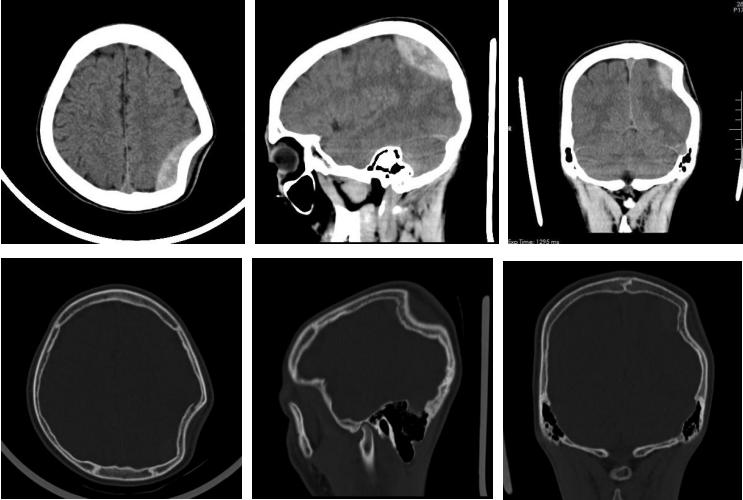

我院神经外七科马赞医师接诊了患者。当时患者的左侧顶枕部出现凹陷性骨折,凹陷范围约为5cm×4cm×1.2cm。

▲术前CT检查所见:左侧顶骨骨质不连,向内凹陷约12mm;左侧顶骨凹陷性骨折,伴左侧顶部硬膜外血肿